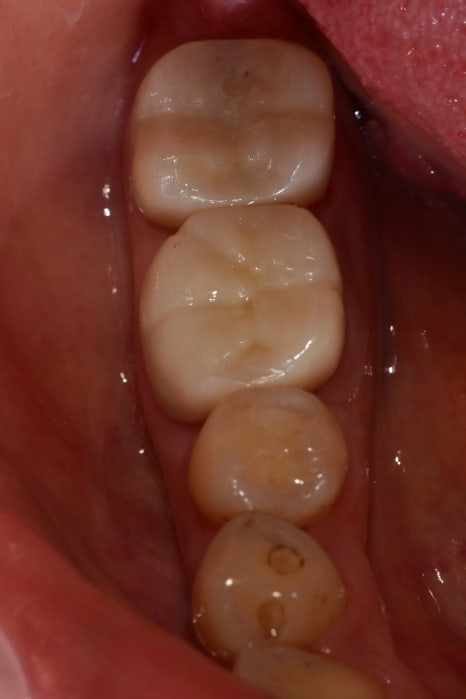

이런 부분들을 제거하고

임시치아 상태에서도 증상이 나타나지 않아

최종 보철까지 완료할 수 있었습니다.

아직까지는 특별한 문제점 없이

경과 관찰 중입니다.